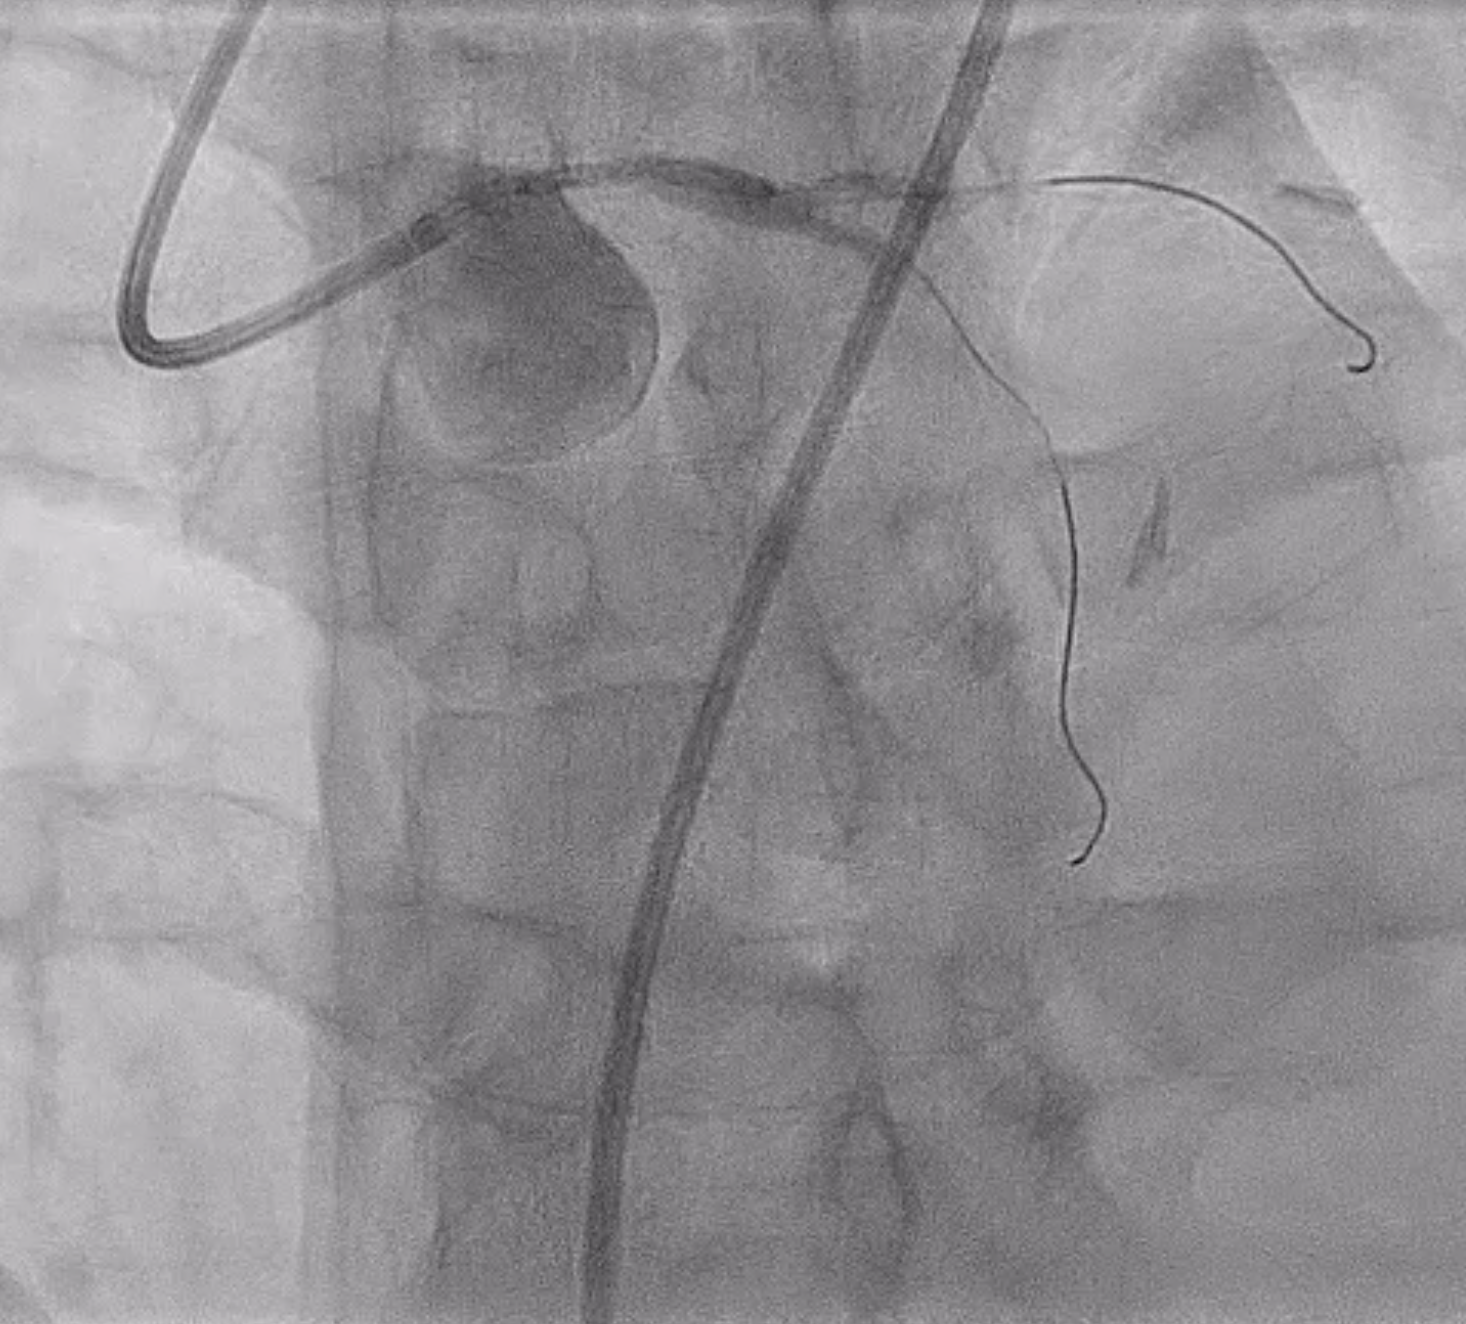

Patient had significant spasm of the bilateral radial arteries so right femoral artery access was obtained. A 6 Fr EBU 3.0 guide catheter was used to engage the left main coronary artery. A Sion wire was advanced into the LAD and a Sion Blue wire was advanced into the left circumflex. Pre-dilation was performed with a 2.5 x 12 mm semi-compliant balloon. IVUS showed MLA of 1.5 mm2 with intramural hematoma and evidence of plaque and thrombus. There was no evidence of SCAD on IVUS imaging. A 4 x 18 mm DES was placed in the left main and post-dilated with a 4.5 x 15 mm and 5 x 8 mm NC balloon. Final angiogram and IVUS confirmed excellent stent expansion/apposition with large MSA (11.8 mm2) and proximal stent edge in the ostium of the left main. Total air kerma was <500 mGy and and DAP was 50 Gy-cm2.